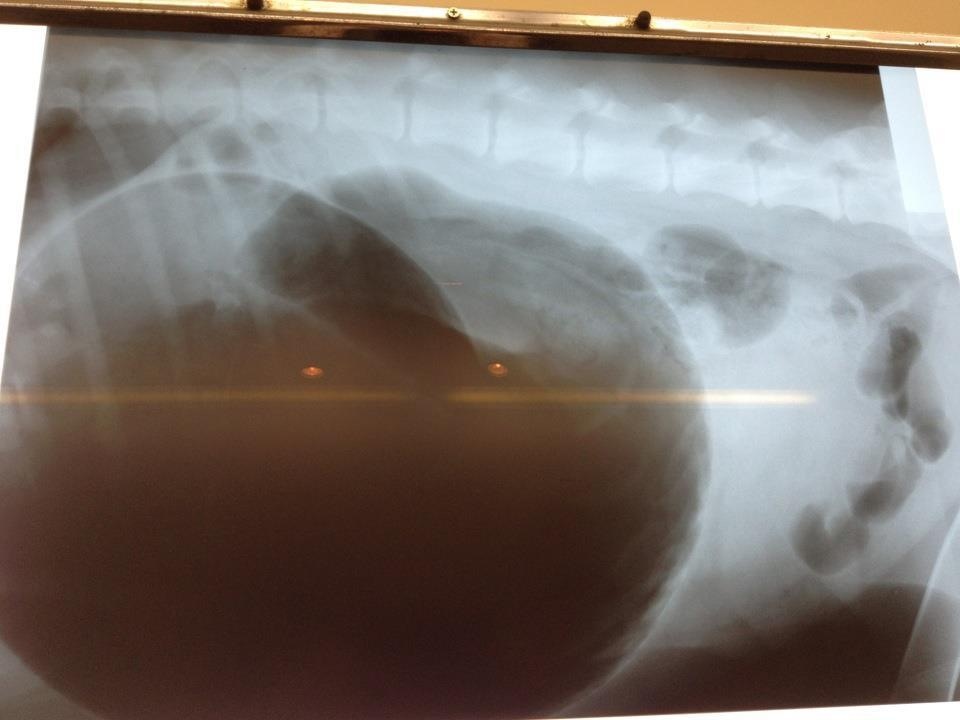

*Lolapalooza* Posted February 24, 2013 Share Posted February 24, 2013 Here is a pic of my dogs X-ray taken 1/2 hour after his first attempt to vomit. He had GDV , lost his spleen and needed blood transfusions x2 but 4 days of intensive care and $8000 later he's fine thank goodness! When we got to the vet it was a junior vet and I had to demand that she see him as it was 10 pm on a Tuesday night and as soon as she saw the X-ray she said that 'there's less than 50% chance of survival with surgery and it is very expensive so we should consider PTS" Ummmmmmmm well doing nothing gives him 0% love!!!!! I spat it and she called in the senior vet thank goodness. That was 7 months ago. Link to comment Share on other sites More sharing options...

*Lolapalooza* Posted February 24, 2013 Share Posted February 24, 2013 Whoops here it is, hope you can see it. It shows a huuuuge stomach Link to comment Share on other sites More sharing options...